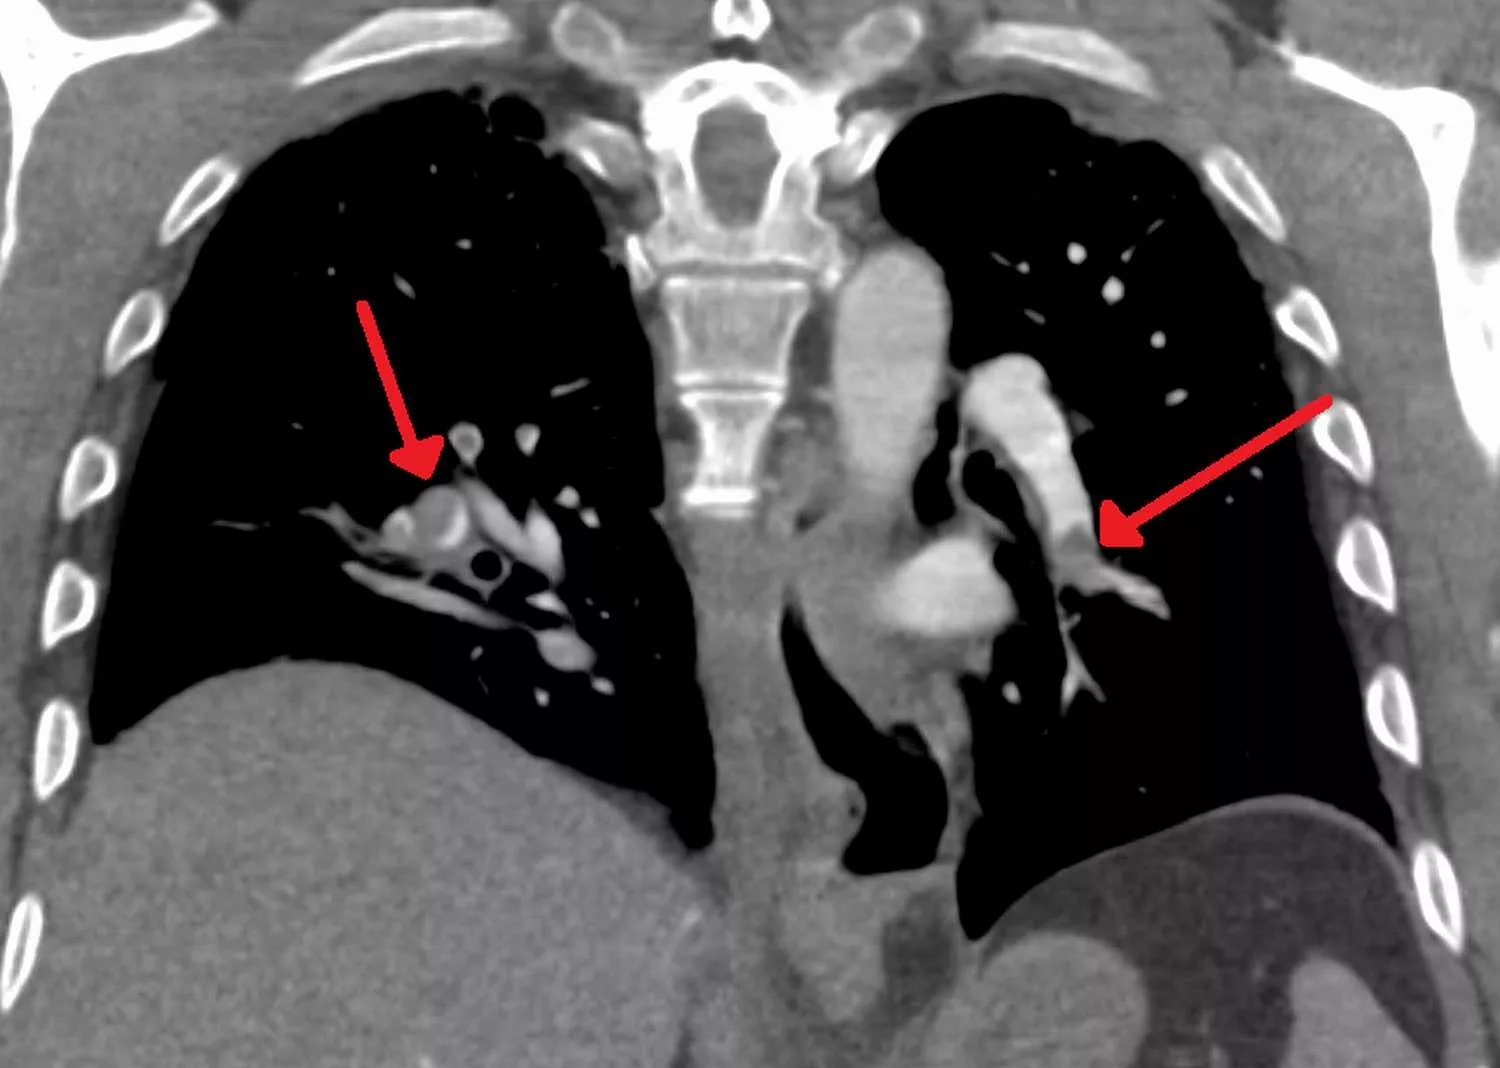

Embólia tüdőben rétegfelvételen

Kétoldali tüdőembólia (kép: James Heilman, MD, liszensz: CC BY-SA, Wikimedia Commons)